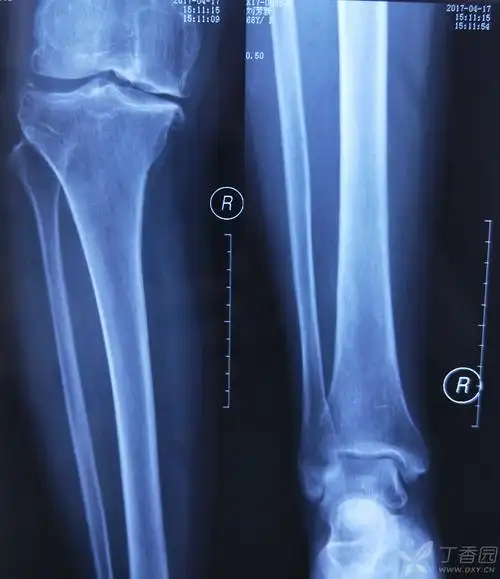

腿骨折的x光照片_有来医生

术前x光片

小腿x线照片

胫骨骨髓炎陈旧骨折如何治疗? [病例帖]